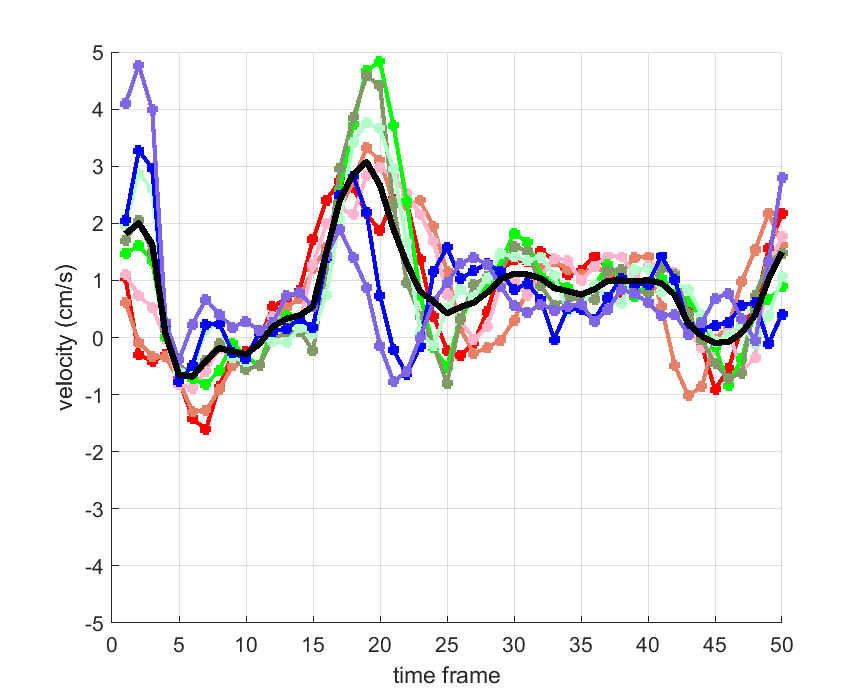

Time courses of the estimated translational component per subject, frame, slice and volume along the 3 velocity directions x, y and z are presented in Fig.6 - Fig.8.